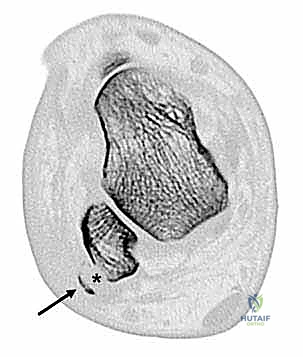

* الميزاب الشظوي (Fibular Retromalleolar Groove): وهو تجويف أو أخدود عظمي يقع خلف عظمة الكعب الخارجية، تنام فيه الأوتار.

* تسطح الميزاب الشظوي (Shallow Fibular Groove): بدلاً من أن يكون الميزاب مقعراً وعميقاً لاحتضان الأوتار، يكون مسطحاً أو حتى محدباً (Congenitally convex)، مما يجعل انزلاق الأوتار مسألة وقت.

في الماضي، كانت الجراحات التقليدية تعتمد على حفر الميزاب العظمي بشكل مباشر من الخارج، مما يؤدي إلى تدمير الغضروف الليفي الزجاجي (Fibrocartilage) الذي يبطن الميزاب، والذي وظيفته تسهيل انزلاق الأوتار بسلاسة. تدمير هذا الغضروف كان يؤدي إلى احتكاك الأوتار بالعظم الخشن، مما يسبب التهابات مزمنة وتمزقات لاحقة.

أما في التقنية غير المباشرة، يقوم الدكتور هطيف بإجراء هندسي عبقري: يتم عمل نافذة عظمية صغيرة أو استخدام مثقاب دقيق (Drill) لإزالة العظم الإسفنجي (Cancellous bone) من داخل عظمة الشظية (من تحت الغضروف)، ثم يتم الضغط (Tamping) على القشرة العظمية المبطنة بالغضروف لتهبط إلى الداخل.

النتيجة؟ ميزاب عميق جداً يحتضن الأوتار بقوة، مع الحفاظ الكامل على الغضروف الأملس السليم بنسبة 100%.